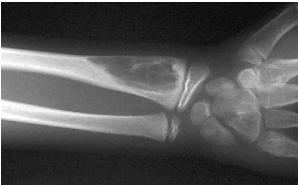

site: Distal tibial

size: Involving most of distal part

matrix: Cortical expansion, radiolucent matrix, well defined, narrow zone of transition

soft tissue involvement: no peristeal reaction